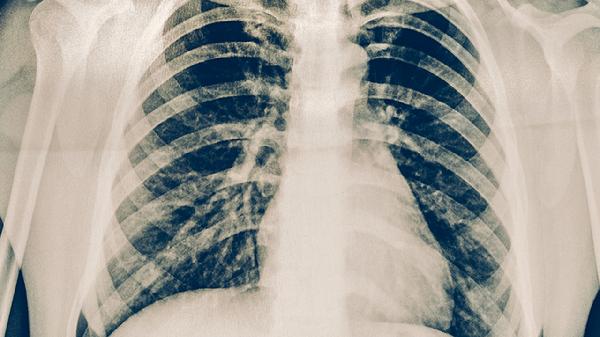

左肺上叶结节可能是良性病变或早期肺癌的表现,常见病因包括炎性假瘤、结核球、错构瘤、肺腺癌等。结节性质需结合影像特征、生长速度及病理检查综合判断。

肺腺癌早期可表现为磨玻璃结节或实性结节,CT可见分叶征、毛刺征等恶性征象。高风险人群包括长期吸烟者、有肺癌家族史者,需通过穿刺活检明确诊断。根据分期可选择胸腔镜肺段切除术、靶向治疗(如吉非替尼片)或化疗(如培美曲塞注射液)。术后需每3个月复查肿瘤标志物。